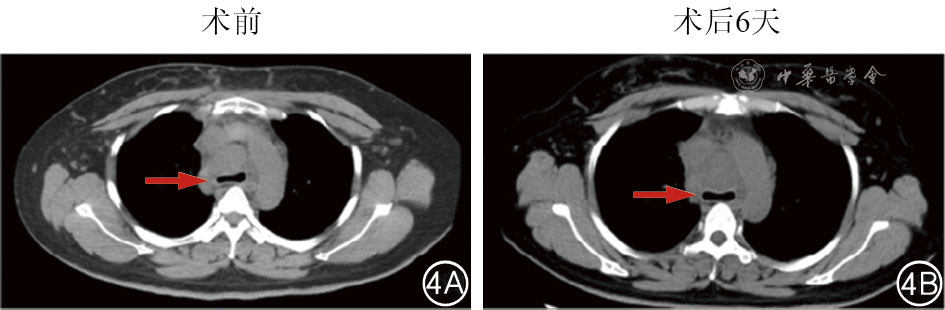

We present a case of a 40-year-old female patient with midline carcinoma, who was admitted for chest pain and cough and diagnosed with concurrent mediastinal and pulmonary metastases. Single-agent chemotherapy proved ineffective and her clinical symptoms aggravated, accompanied by tracheal and superior vena cava compression. Following multidisciplinary consultation, CT-guided 125Ⅰ seed implantation was initially performed. Local tumors regressed postoperatively while partial pulmonary metastatic lesions progressed, prompting seed reimplantation combined with bronchial arterial chemoembolization, followed by concurrent anlotinib targeted therapy and sintilimab immunotherapy. After six months of comprehensive treatment, the thoracic tumors resolved, lymph nodes shrank, radiological evaluation indicated partial response, and the patient's clinical symptoms were significantly relieved. This case demonstrates that the integrated regimen of interventional local therapy plus targeted and immunotherapy offers a viable therapeutic approach for inoperable midline carcinoma patients with refractory conventional chemotherapy, enabling rapid symptom relief and improved treatment efficacy.